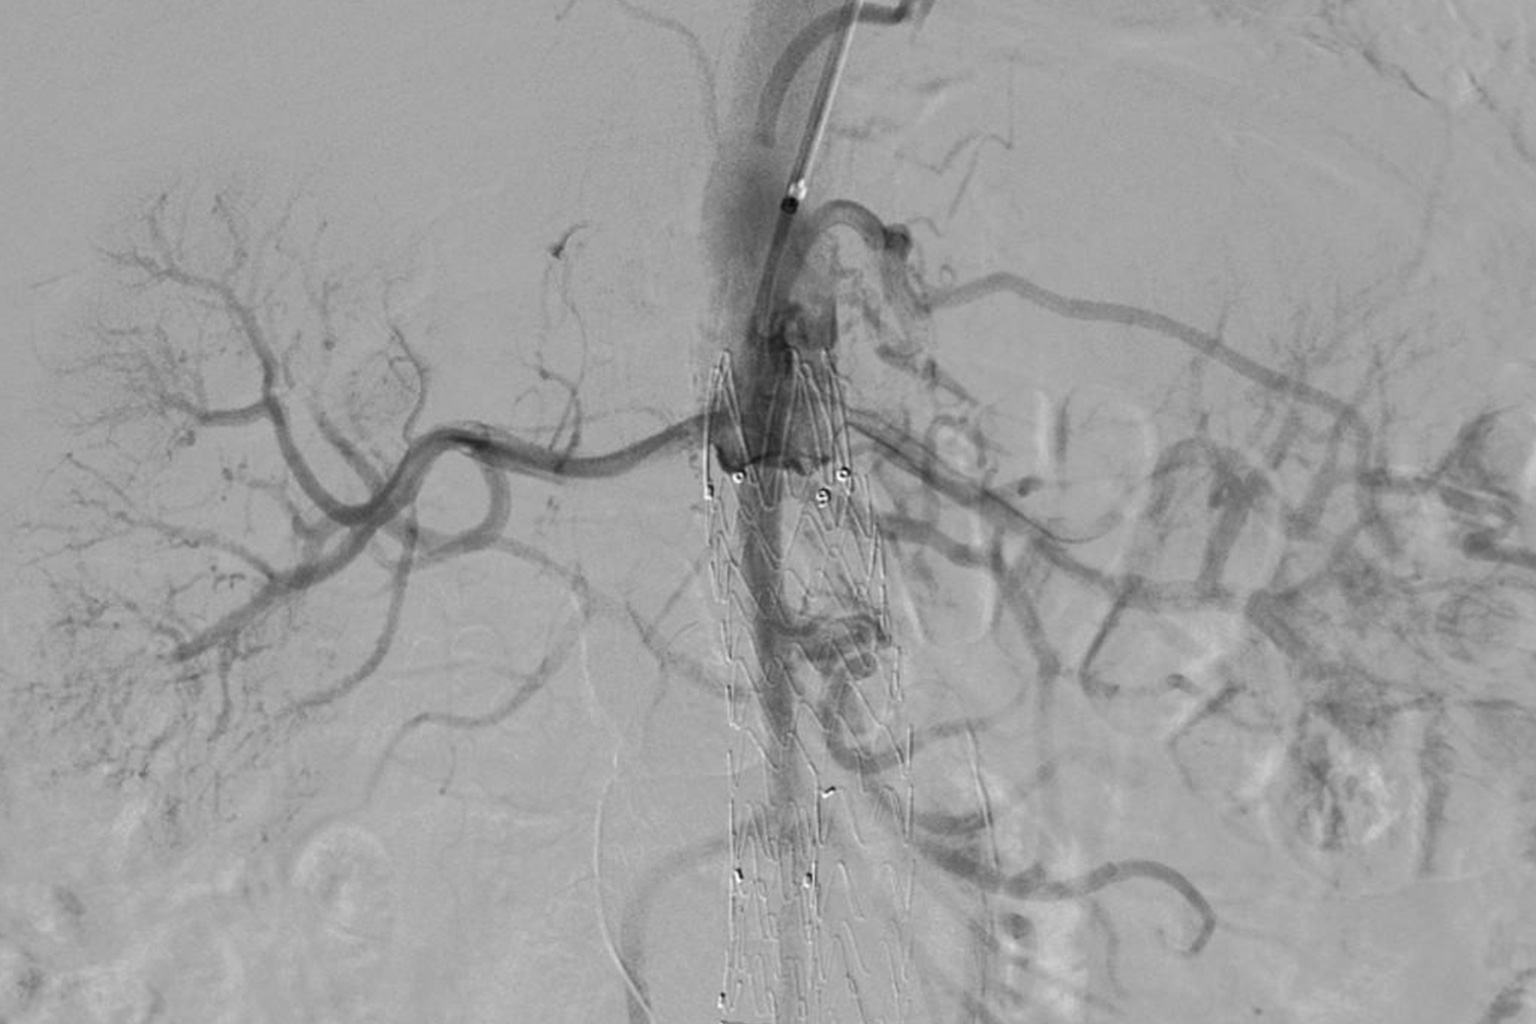

PE Peer Meeting 2026: confronto multidisciplinare sull’embolia polmonare e tecniche interventistiche

Il 14 maggio 2026, presso l’Hotel Royal Continental di Napoli, si è svolto il PE Peer Meeting, evento dedicato allo stato dell’arte dell’embolia polmonare e alle più moderne tecniche di trattamento interventistico percutaneo. L’incontro, organizzato da Penumbra, ha riunito specialisti